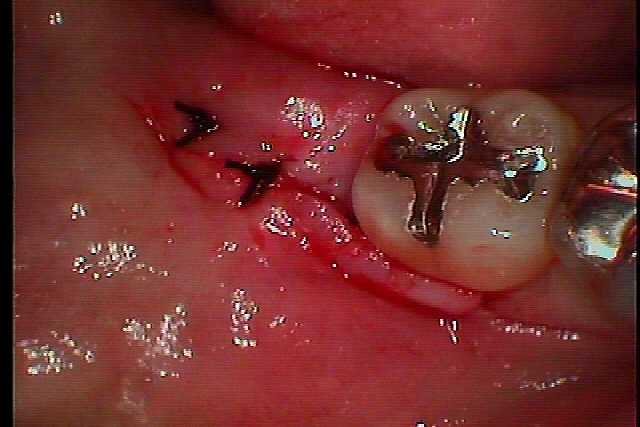

右下水平埋伏歯の難抜歯 全く見えていないところに歯が存在していますが、、、、|お知らせ |広島市安佐南区の歯科医院 右下水平埋伏歯の難抜歯 全く見えていないところに歯が存在していますが、、、、 トップ お知らせ・ブログ お知らせ 右下水平埋伏歯の難抜歯 全く見えていないところに歯が存在していますが、、、、 右下水平埋伏歯の難抜歯 全く見えていないところに歯が存在していますが、、、、 ここに親不知が埋まっています デンタルレントゲンにて 麻酔をかけて開けていきます このように見えてきます 抜歯を行いました 2針縫合して終了となります 1週後に抜糸していきます Web診療予約 初めての方へ 選ばれ続ける理由 院内設備について 歯が痛いしみる一般歯科 歯がぐらぐらする歯周病 健康な歯を保ちたい予防歯科 子供の虫歯予防をしたい小児歯科 銀歯をセラミックに審美歯科 白い歯を目指しませんか?ホワイトニング 矯正専門医がいるので安心矯正歯科 抜けた歯を補いたいインプラント・入れ歯 医院案内 スタッフ紹介 メリィハウス歯科クリニックオフィシャルホームページ ラベンダー歯科クリニックオフィシャルホームページ お知らせ・ブログ ホーム 診療科目 一般歯科 歯周病治療 予防治療 小児歯科 審美治療 ホワイトニング 矯正歯科 入れ歯・インプラント マウスピース矯正 初めての方へ 院長・スタッフ 設備紹介 医院案内・アクセス メニューを閉じる